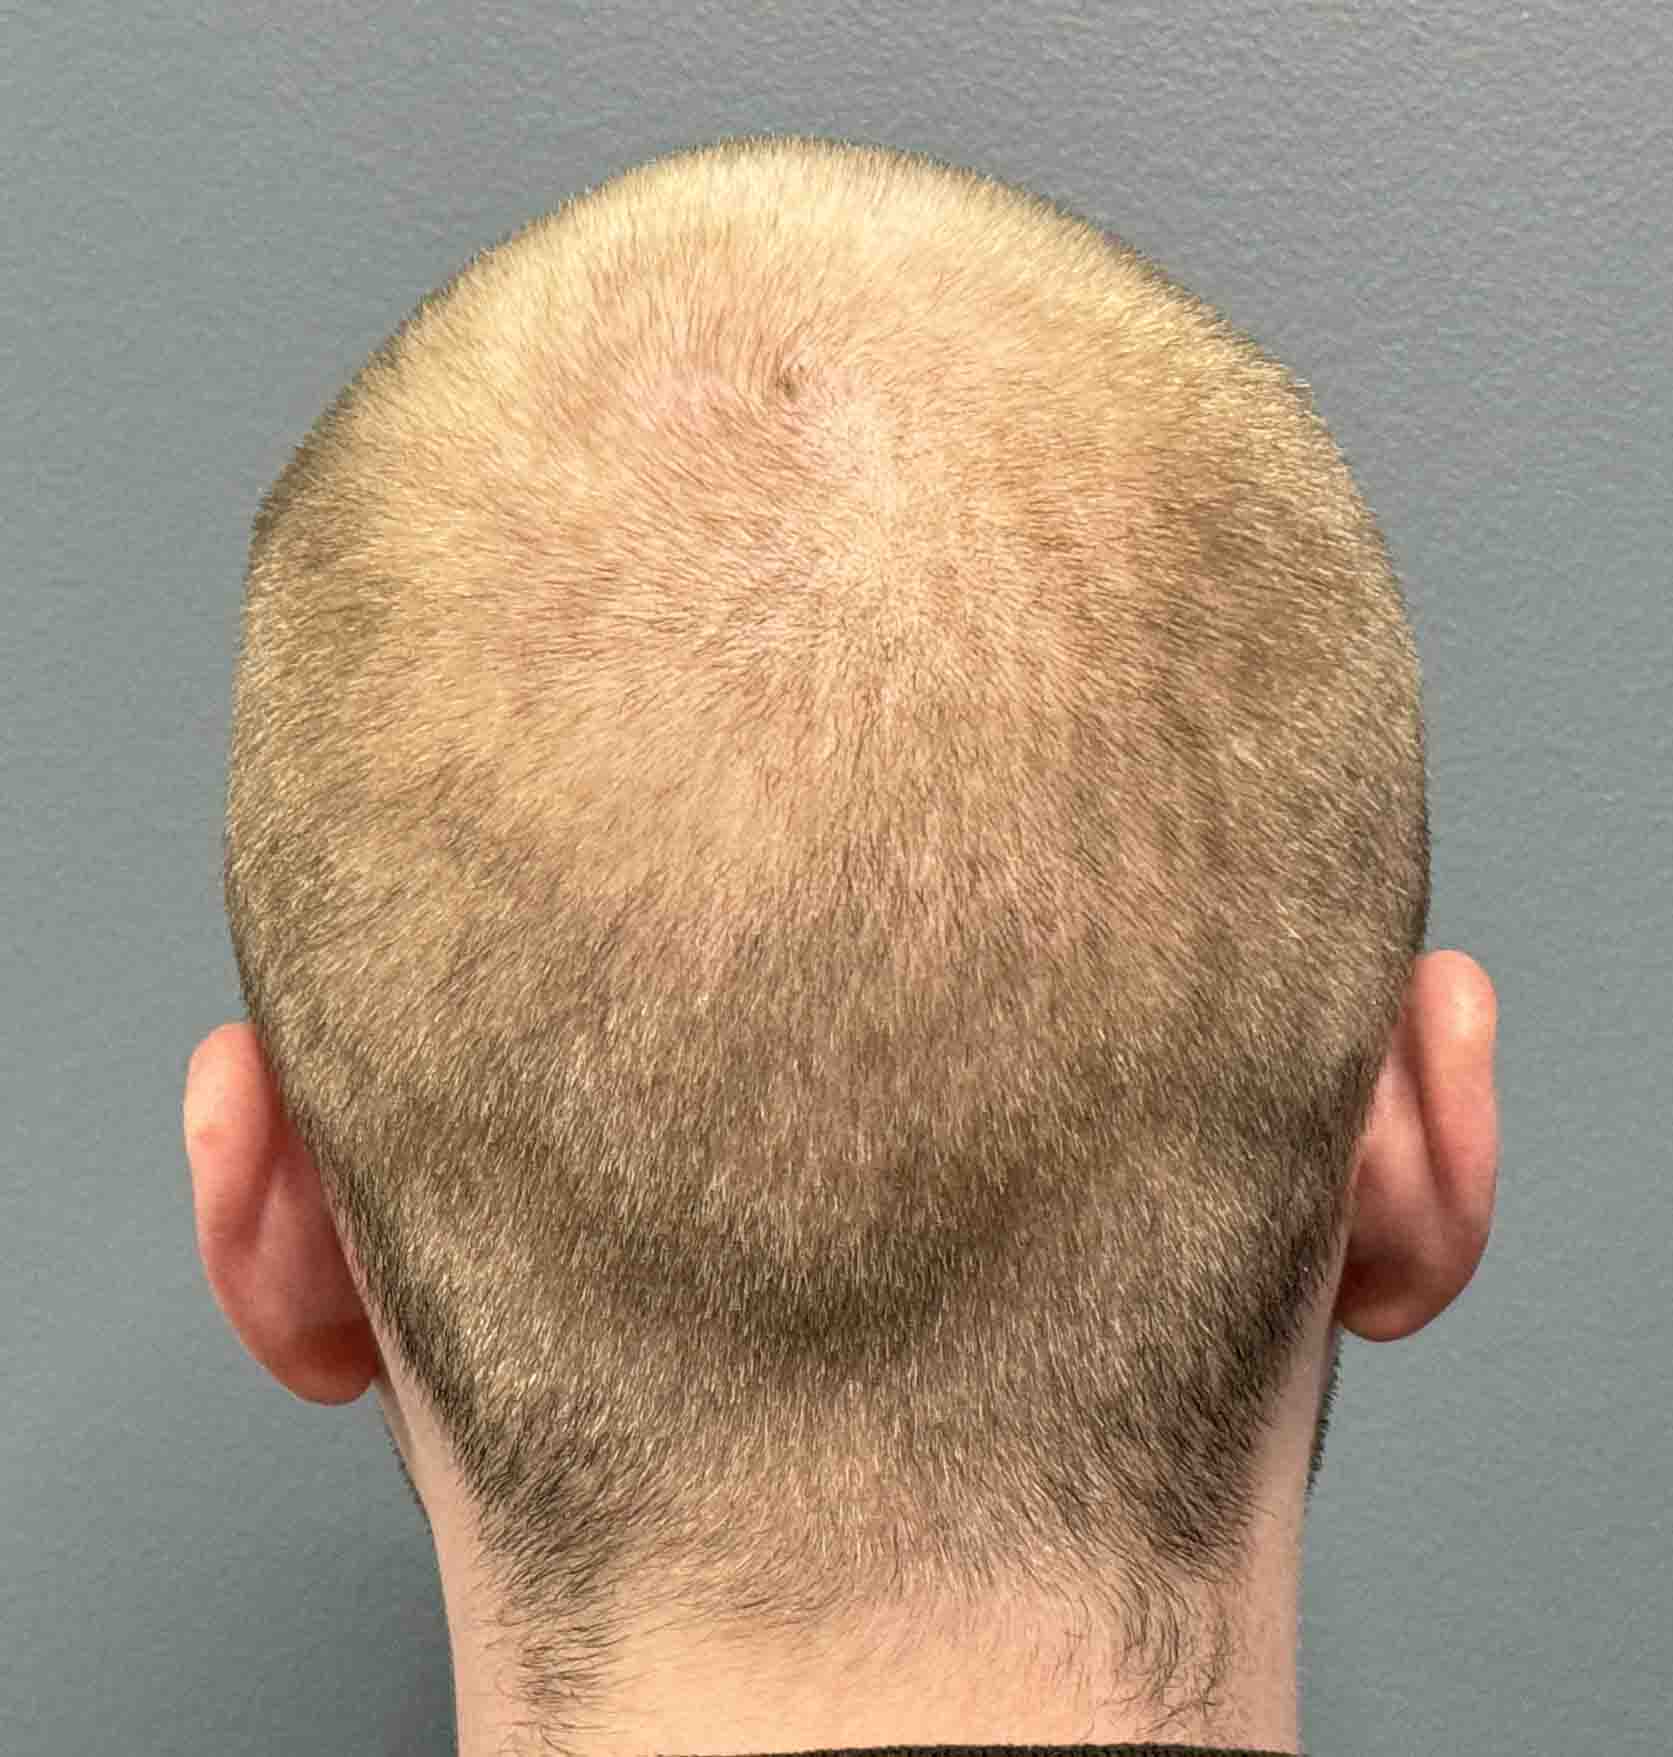

Patient 100

Desire for reshaping of an asymmetric flat back of the head in a shaved head male.

A combined back of the head reshaping procedure was done with a custom skull implant, sagittal ridge reduction and a right temporal muscle reduction.

Desire for reshaping of an asymmetric flat back of the head in a shaved head male.

A combined back of the head reshaping procedure was done with a custom skull implant, sagittal ridge reduction and a right temporal muscle reduction.